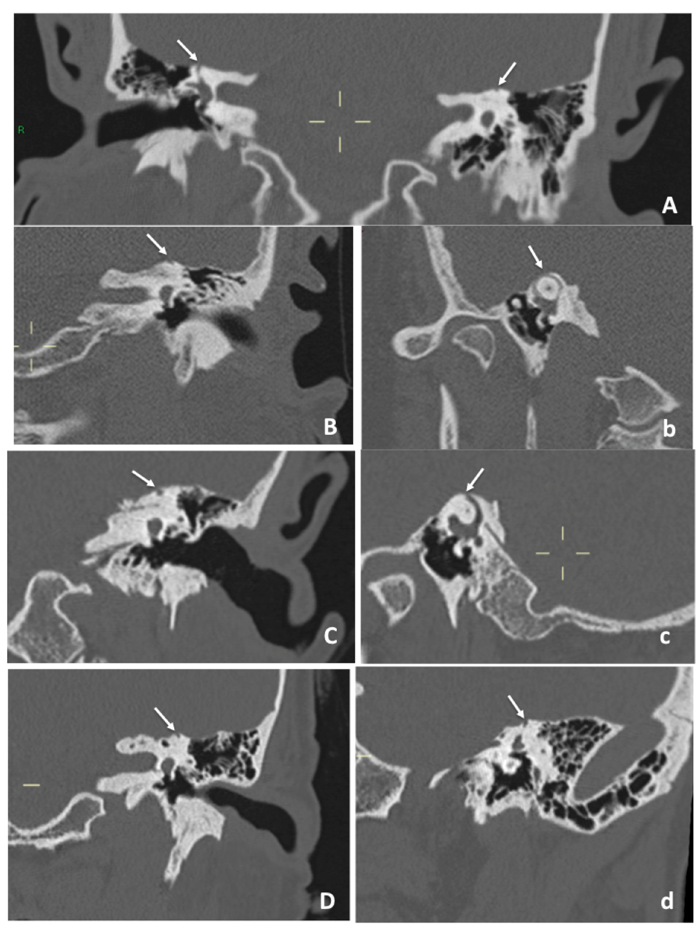

High-resolution CT imaging of the temporal bones and vestibular evoked myogenic potentials (VEMPs) can be used to corroborate clinical findings. On fine-cut (0.5mm collimation or less) CT imaging reformatted to include cuts in the plane of and perpendicular to the superior semicircular canals, identification of bony dehiscence over the superior semicircular canal indicates SSCD [2] (see Figure 1). A full vestibular assessment is usually utilised in all patients suspected of having SSCD; however, VEMPs are the most useful vestibular diagnostic test. Both cervical and ocular VEMP thresholds are significantly lower in patients with SSCD, aiding diagnosis [3,4].

Figure 1. CT scans of a few of the patients with SSCD showing coronal (A, B, C and D) and sagittal and parasagittal oblique (b, c and d) sections of the temporal bone. The dehiscence is marked with white arrows and its extent can vary; in A the defect is bilateral.

Among the most important aspects of managing the patients with SSCD are the utilisation of meticulous diagnostic batteries, sufficient trial of vestibular rehabilitation and very careful consultation. In our unit, the detailed history and clinical examination, which will raise the strong suspicion of SSCD, will be followed by high resolution CT of the temporal bones (Figure 1) as well as audiological and vestibular assessment including pure-tone audiometry (Figure 2C), tympanometry, cVEMPS (Figure 2A), dynamic posturography and lately six-canal video-Head-Impulse-Test (vHIT) (Figures 2B and b) and visual subjective vertical. Following the diagnosis of SSCD, the symptomatic patient will be referred for vestibular rehabilitation; should there be no improvement of the vestibular symptoms, the option of surgical intervention will be thoroughly explained, mainly to make the patient aware of the procedure, the related risks and benefits as well as the realistic expectations.